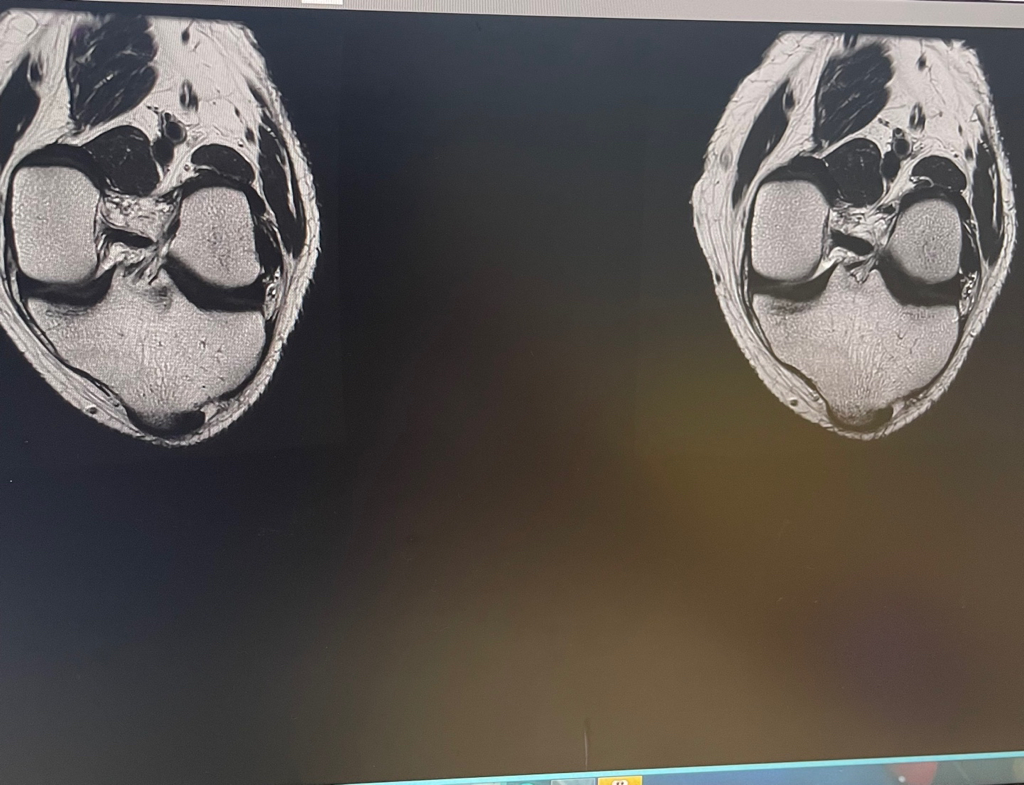

무릎 mri 원형원골인지 봐주실 수 있을까요

무릎이 너무 자주 아파서 mri를 찍어봤는데 무릎 연골에 이상이 있을까요

무릎이 선천적으로 원형연골인지 봐주시면 감사하겠습니다

MRI 판독에는 퇴행성 연골 손상, 바깥쪽 원판형 반월상 연골 이 의심된다고 적혀 있습니다.